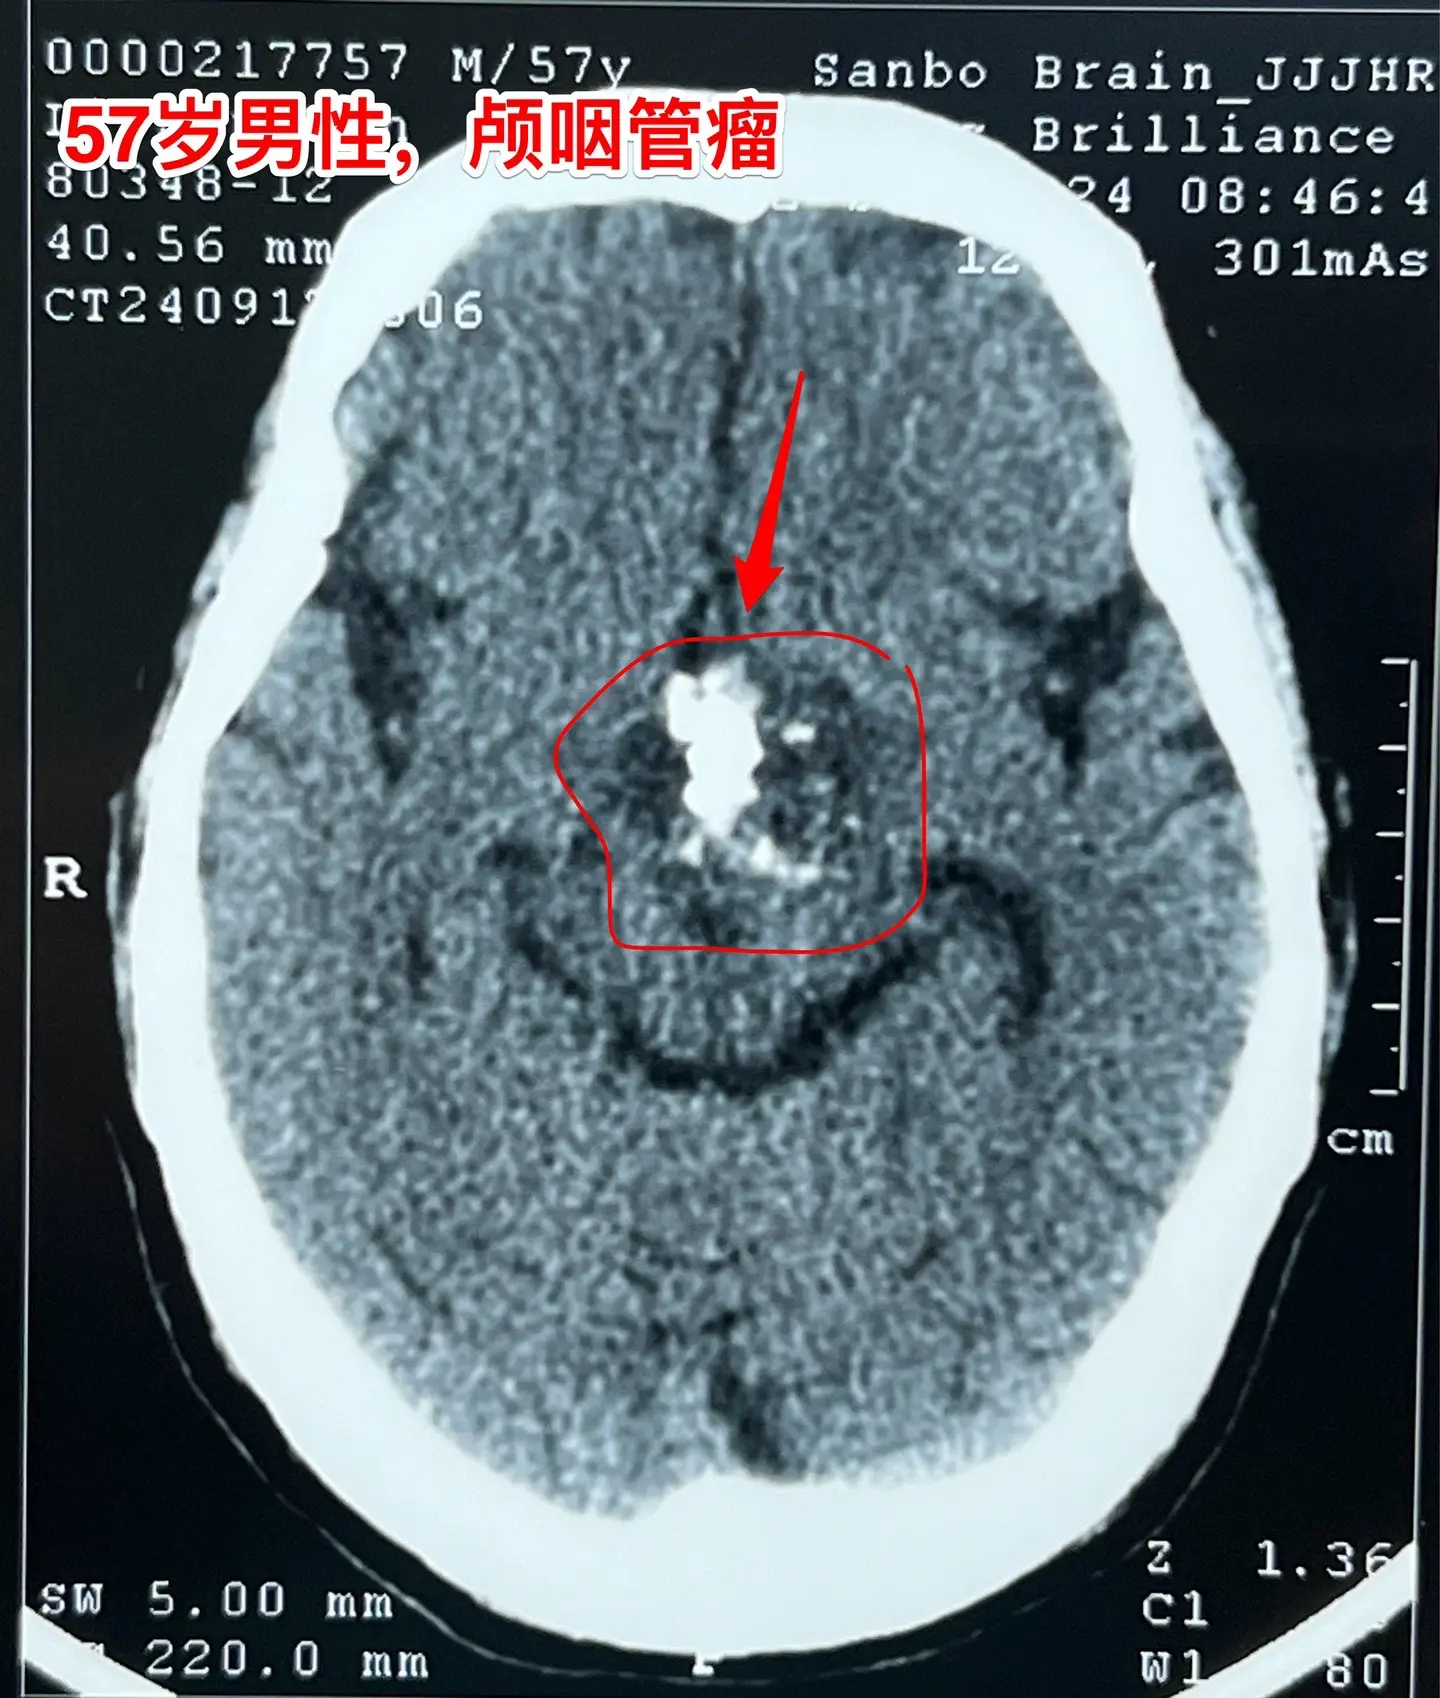

57岁男性,颅咽管瘤导致视力下降。病人因视力下降、消瘦到外院检查发现颅咽管瘤。如图所示,肿瘤体积比较大,有大量的钙化斑,是典型的造釉性颅咽管瘤。2024.9.20在我院行开颅手术,将颅咽管瘤完全切除。手术后患者视力明显改善了。十一前已经出院了,出院前体重有增长。